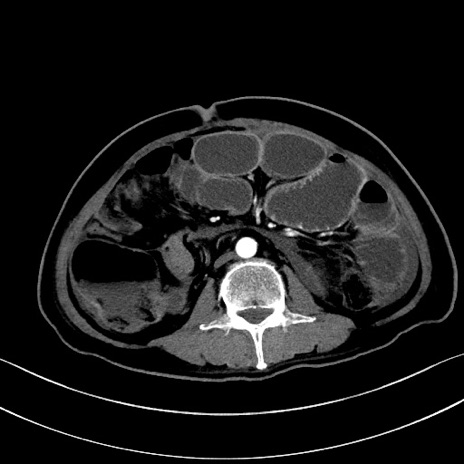

症例28(横断像)

【症例】60歳代男性

【主訴】嘔吐

【現病歴】胃癌にて胃全摘後。食思不振が悪化し、夜中に嘔吐することがある。

【既往歴】胃癌、胃全摘、脾摘、胆摘後

【データ】WBC 5900、CRP 10.56